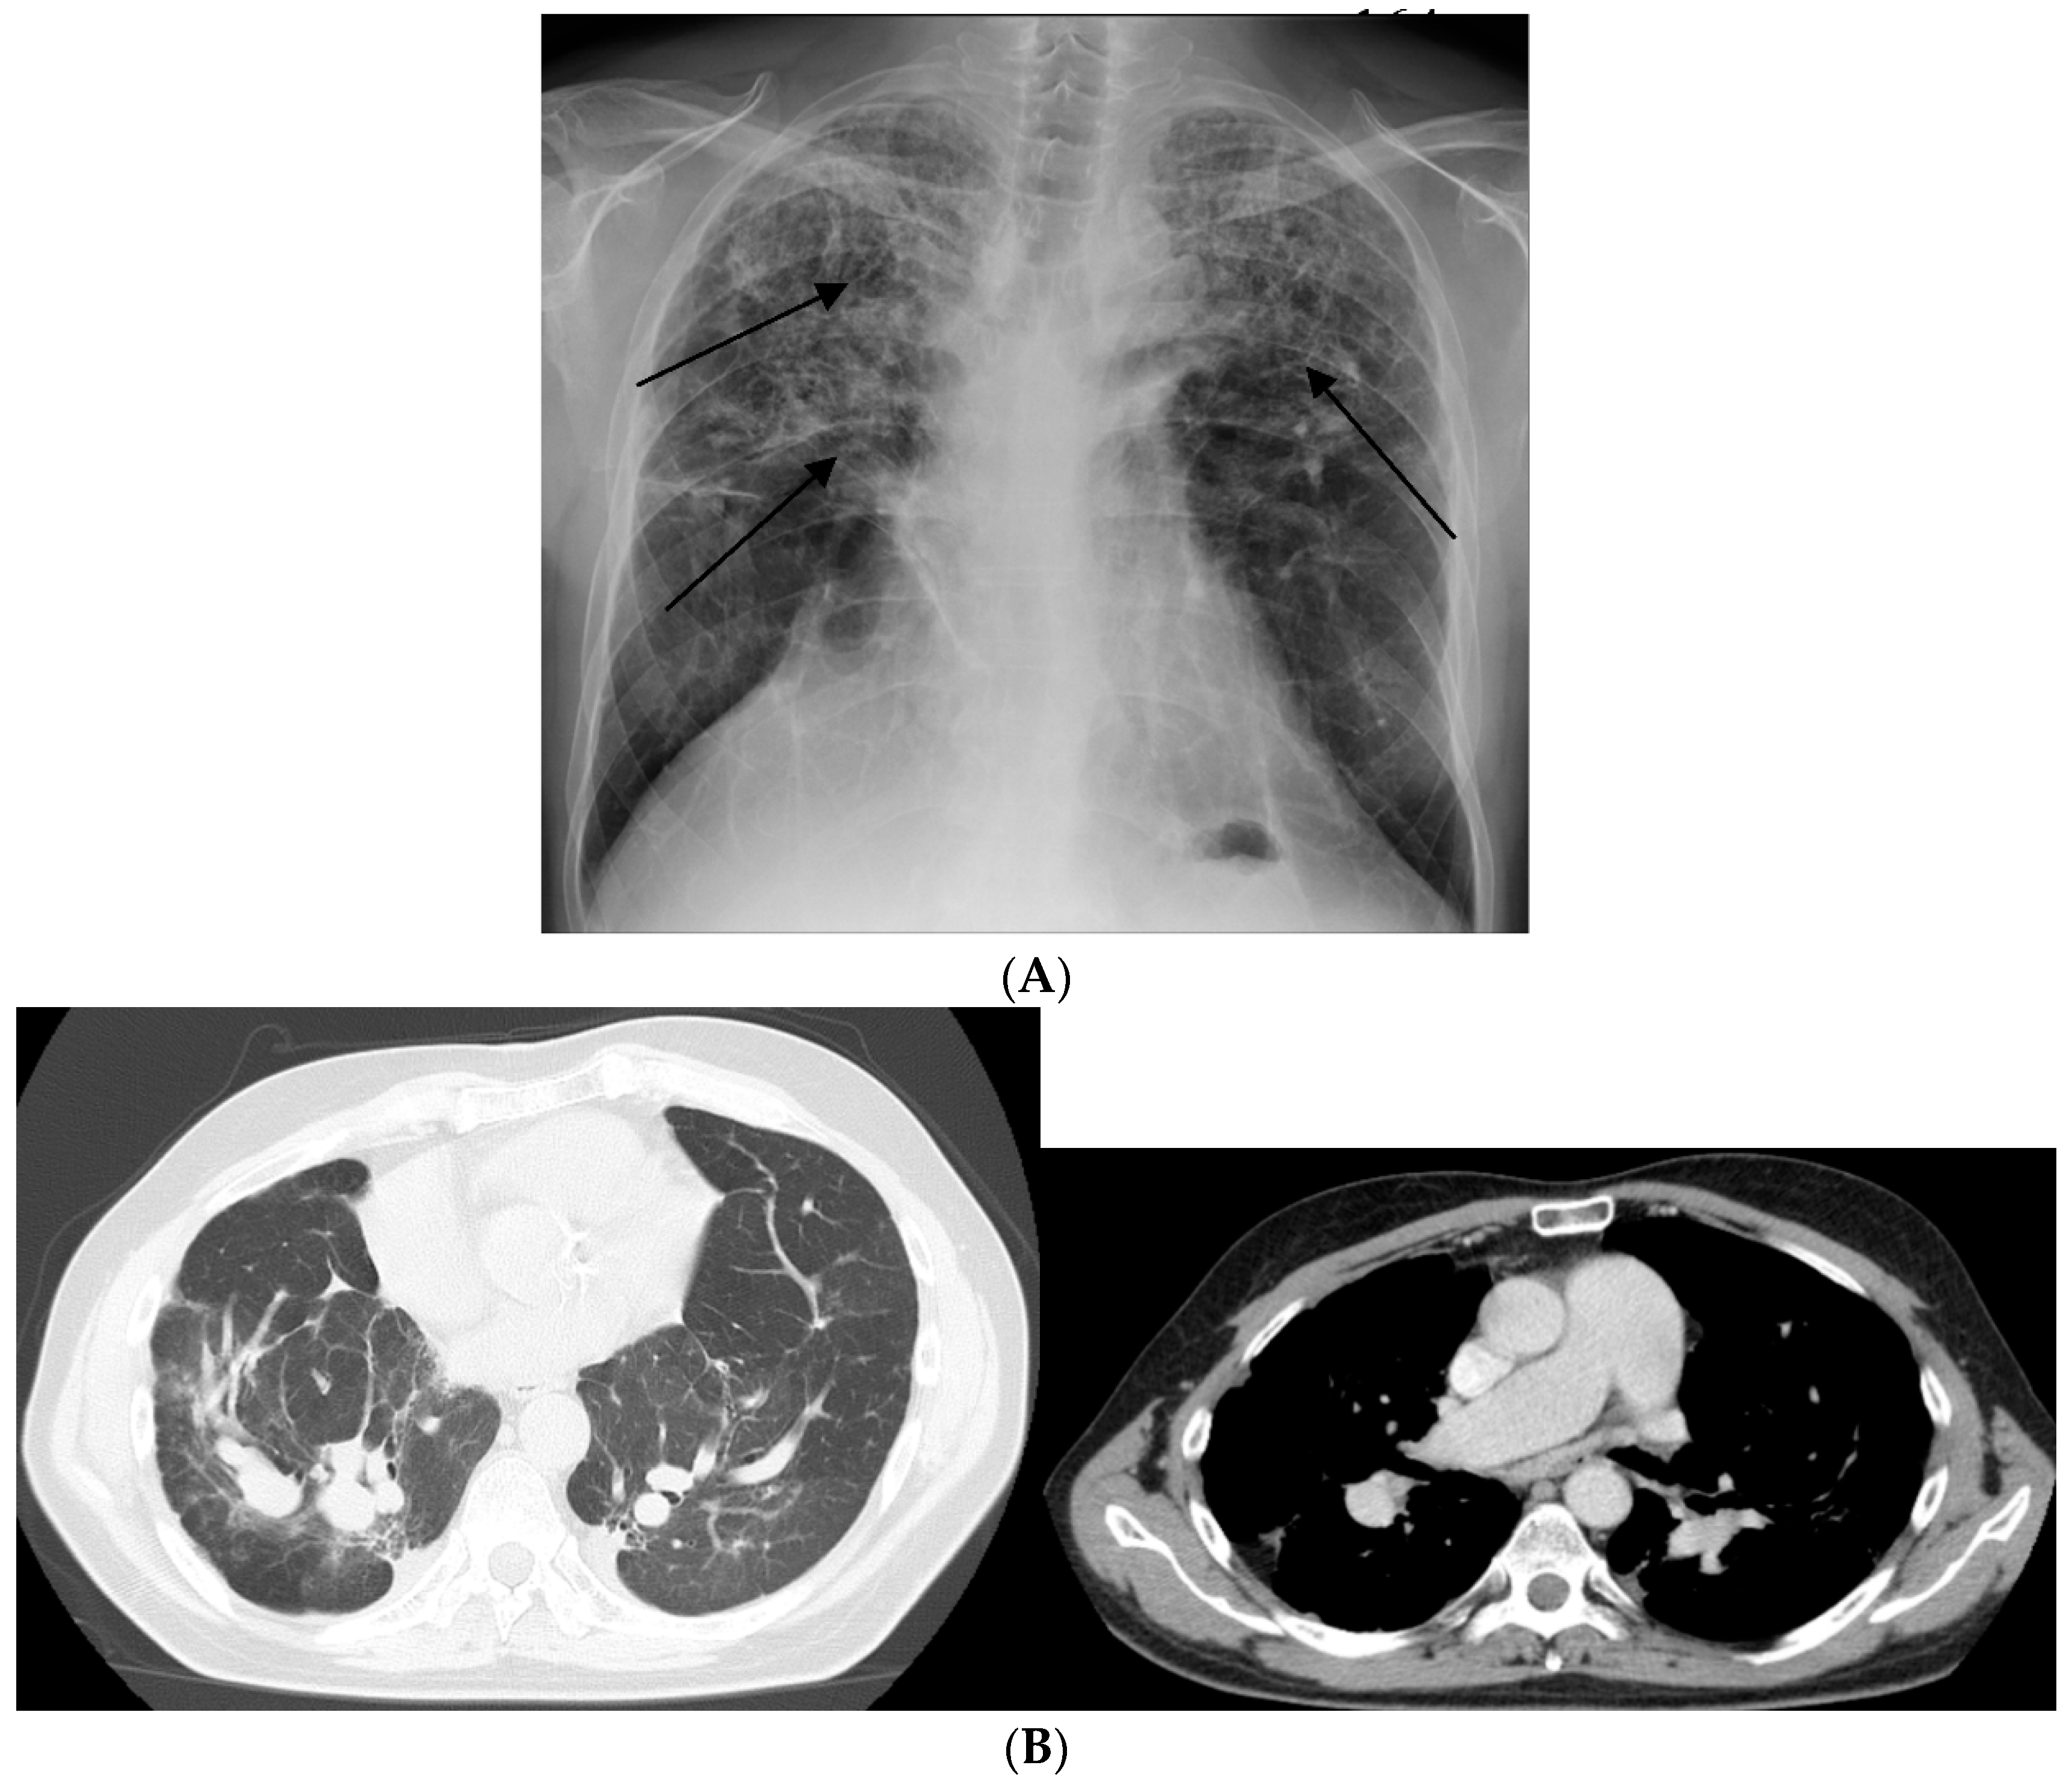

1.1. Lung

- Nunes, H.; Uzunhan, Y.; Gille, T.; Lamberto, C.; Valeyre, M.; Brillet, P.-Y. Imaging of sarcoidosis of the airways and lung parenchyma and correlation with lung function. Eur. Respir. J. 2012, 40, 750–765. [Google Scholar] [CrossRef] [PubMed]